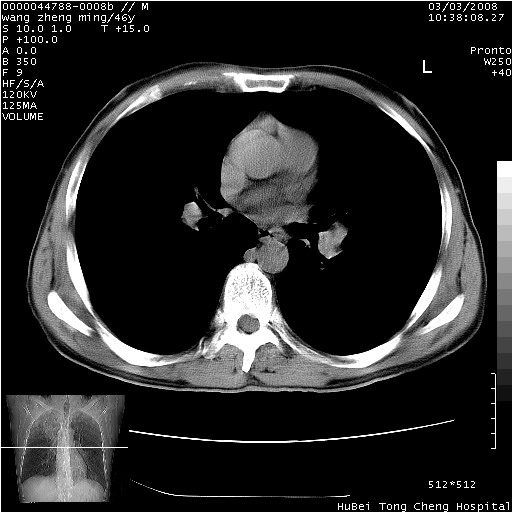

以下是引用卜一在2008-3-22 1:37:00的发言:[br]右肺实质性肿块,边缘不整,明显见毛刺征 分叶征及胸膜凹陷征,右上叶支气管明显变窄,远端散在的片状 斑片状实变影。另:左肺门较大肿块,支气管受累 变窄,远侧见阻塞性肺炎。纵隔内见肿大淋巴结。多考虑:右肺周围性肺癌伴左肺门 纵隔淋巴结转移!